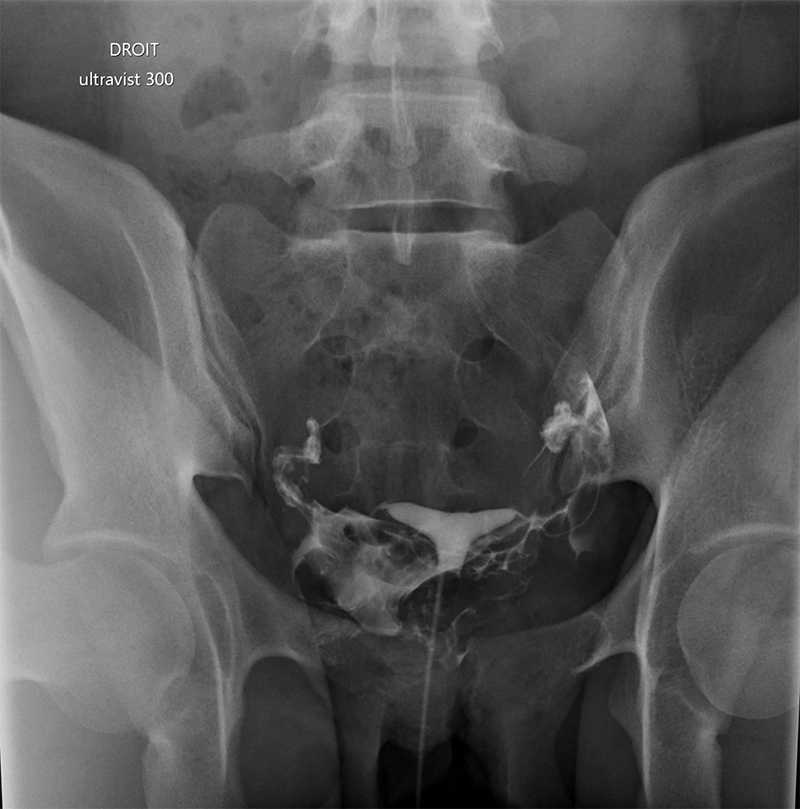

Il s’agit d’un examen d’imagerie médicale utilisant les rayons X avec opacification par du produit de contraste de la cavité utérine et des trompes.

Plusieurs clichés sont alors effectués, avant puis après injection de produit de contraste, afin de visualiser la progression.